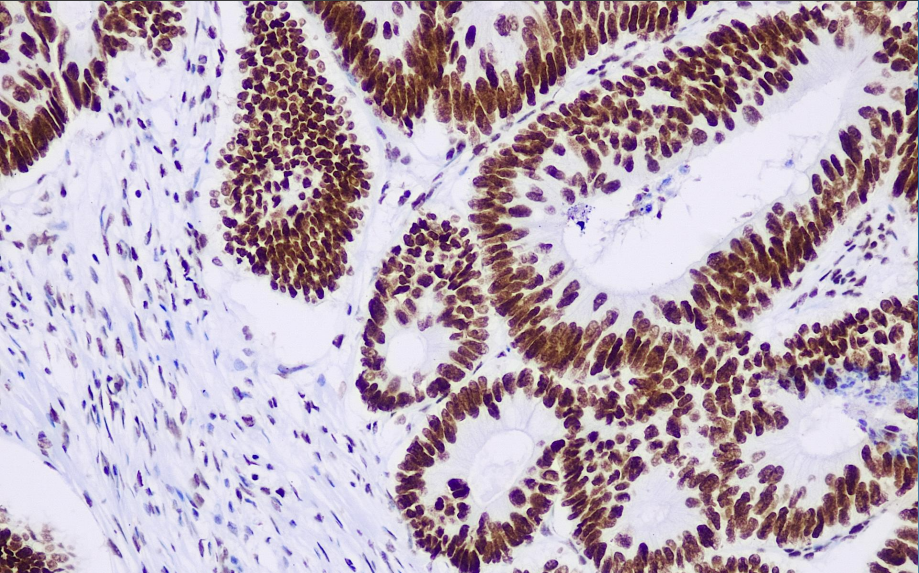

Cellular localization: nucleus

Positive control: Colorectal cancer

The MSH2 antibody reagent can specifically bind to the MSH2 molecular antigen. The immunohistochemical kit containing the MSH2 antibody reagent is suitable for the precise diagnosis of Lynch syndrome (HNPCC) and microsatellite instability (MSI-H) tumors.